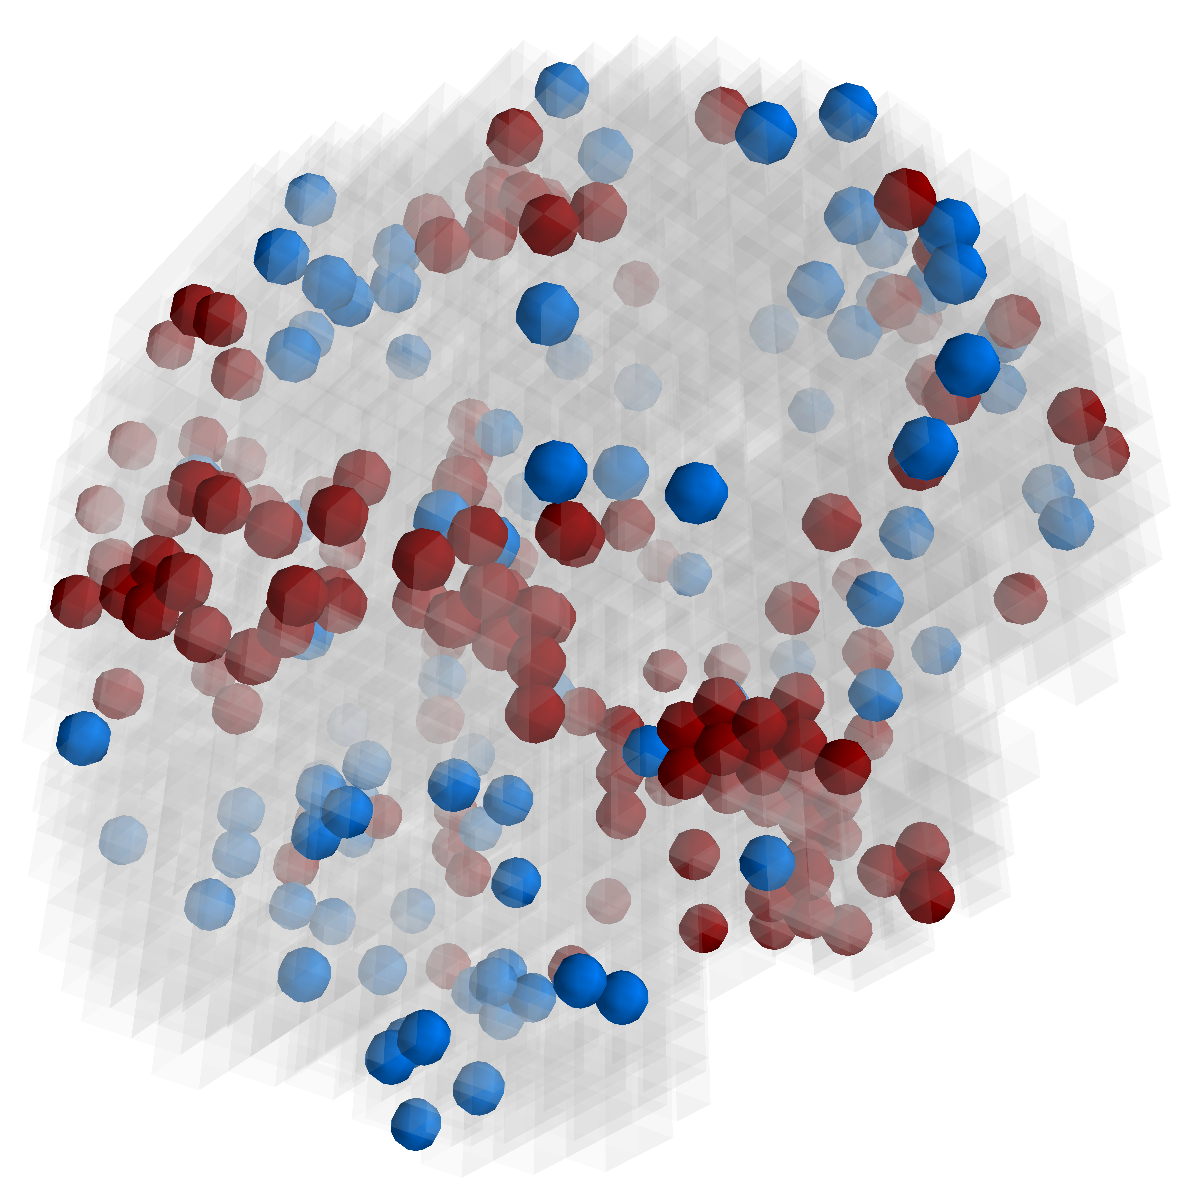

Figure 3: Stability of selected voxels across different folds of the cross-validation. The results of 5 different folds are shown in (a)-(e). The voxels with positive β𝛽\beta are in brown, negative ones are in blue. The common/overlapped voxels selected in all 10 folds are shown in green (f). The top row illustrates voxels selected by the lasso model, the mid row illustrates those of GFL and the bottom row shows those of n2superscript𝑛2n^{2}GFL.

Feature Stability. In Figure 3, we show the selected voxels across different folds of CV333Here, parameters were determined by accuracy. Similar results were observed using parameters producing same level of sparsity.. As shown, the selected voxels by lasso vary much across different folds, whereas the selected voxels by GFL are more stable. However, by assuming the positive correlation between the features and the disease labels in n2superscript𝑛2n^{2}GFL, we further increase the stability. To quantitatively evaluate the stability gain, we denote the variables of the k𝑘kth fold of CV as 𝜷(k)𝜷𝑘\boldsymbol{\beta}(k). We introduce two measurements here. In (?), the Estimation Stability (ES) is proposed to measure the stability of the estimation

where ##\# is the number of elements in a set. In Tab. 3, both measurements quantitatively suggest n2superscript𝑛2n^{2}GFL obtains much more stable voxels due to the consideration of the correlation between the features and the disease labels 444We notice that, in (?), the stability is computed using the top 50 positive voxels because these voxels are believe to be the most atrophied ones. By computing the stability of all non-zero voxels, the mDC of GFL drops around 30%percent3030\%. This clearly shows that the instability is caused largely by the undesirable voxels that disagree with the correlation prior (those scattered blue voxels in the mid row)..